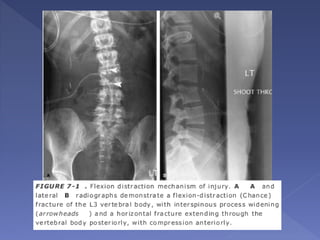

 most common at the thoracolumbar junction

 separation in a cranial-caudal direction

 Mechanism - result of hyperflexion of the

upper thoracic spine while the lower spine

remains relatively fixed

 classically caused by a deceleration-type

motor vehicle accident

 The resultant fracture has been classically

described as the “Chance fracture”

“Classic Chance fracture” :

 The classic Chance fracture accounts for approximately 50%

of Chance-type injuries

 A “classic” Chance fracture - consists of a pure osseous

injury in which there is a horizontal split through the spinous

process, lamina, pedicles, resulting in a small anteroinferior

corner fracture of the lower vertebral body

 acutely unstable

 purely an osseous disruption; it also has excellent healing

potential with good prognosis for long-term stability

 Incidence of neurologic deficit is low, estimated at 10%

 AP radiographs - “double” spinous process,

interspinous distance widening, and horizontal

fractures through the pedicles

 lateral radiograph is often unreliable due to

overlap